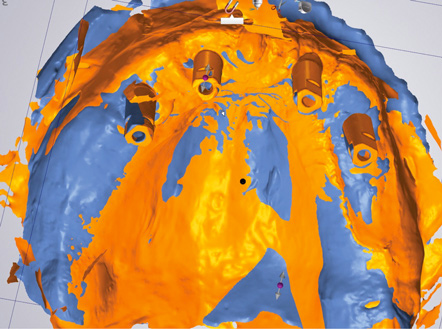

Fig 22. Heat-scan analysis. This image is a conventional impression taken with impression copings; the accuracy of the implant position was confirmed with a verification jig. Scan flags were then placed on the conventional/poured model. Figure 23 is an intraoral optical scan with scan flags. Comparison of the models with scan flags indicates in red/magenta poor correlation between the two methods.

Fig 23. Heat-scan analysis. Figure 22 is a conventional impression taken with impression copings; the accuracy of the implant position was confirmed with a verification jig. Scan flags were then placed on the conventional/poured model. This image is an intraoral optical scan with scan flags. Comparison of the models with scan flags indicates in red/magenta poor correlation between the two methods.